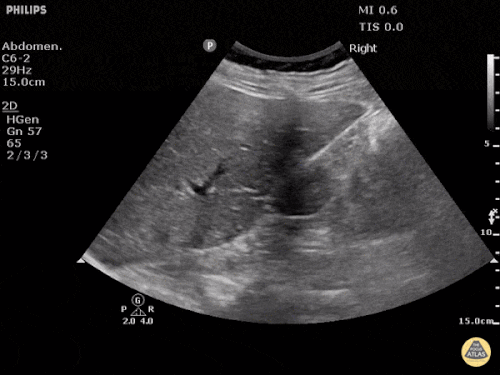

FAST: Morrison Alanı ve Normal FAST Görüntüleri

Normal FAST – Sağ Üst Kadran (RUQ)

Normal FAST – Sol Üst Kadran (LUQ)

Değerlendirmede amaç hipoekoik veya anekoik sıvı saptamaktır. Hipotansif travma hastasında peritoneal boşlukta görülen hipoekoik sıvı genellikle kan olarak kabul edilir.